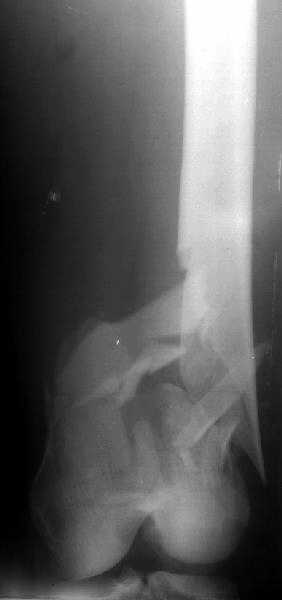

I attached an example of C2 fracture with result of the same technique in 5 months.

Enclosing a recent intraop picture